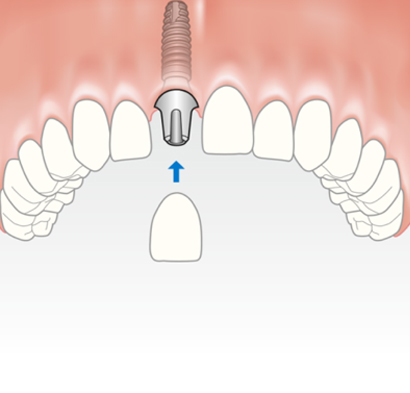

The process of Dental Implants involves placing a titanium cylinder which mimics the root of your tooth into the jaw bone which is connected to an aesthetic tooth coloured crown with the help of a custom fabricated part called an abutment. The success of implant treatment depends on the titanium cylinder fusing into your jaw bone(osseointegration), planning of a custom abutment to achieve good gum aesthetics and fabricating a natural looking crown/crowns to match your facial and dental profile.

Those who have a single tooth missing often choose Dental Implants for replacement as it comes closest to imitating a natural tooth. Implants are also long-lastingly sturdy since they are fused to the jawbone and can stably stand on their own. Dr Bopanna offers uncompromising attention to detail, and uses the latest equipment to craft your new tooth.

Single tooth replacement is normally carried out in three stages. The failing tooth is extracted and an implant is placed into the socket or it can be placed after complete healing has occurred (3 months). After allowing the bone and gum to heal around the implant a scan body is attached to the implant/s and a 3d digital impression is taken. The scan is then uploaded to either Atlantis or Exocad and the abutment is designed, after which the stl file(3D file) is used to design the crown which fits on top of the implant. All of these stages can be carried out in the single appointment depending on need and condition of the patient.